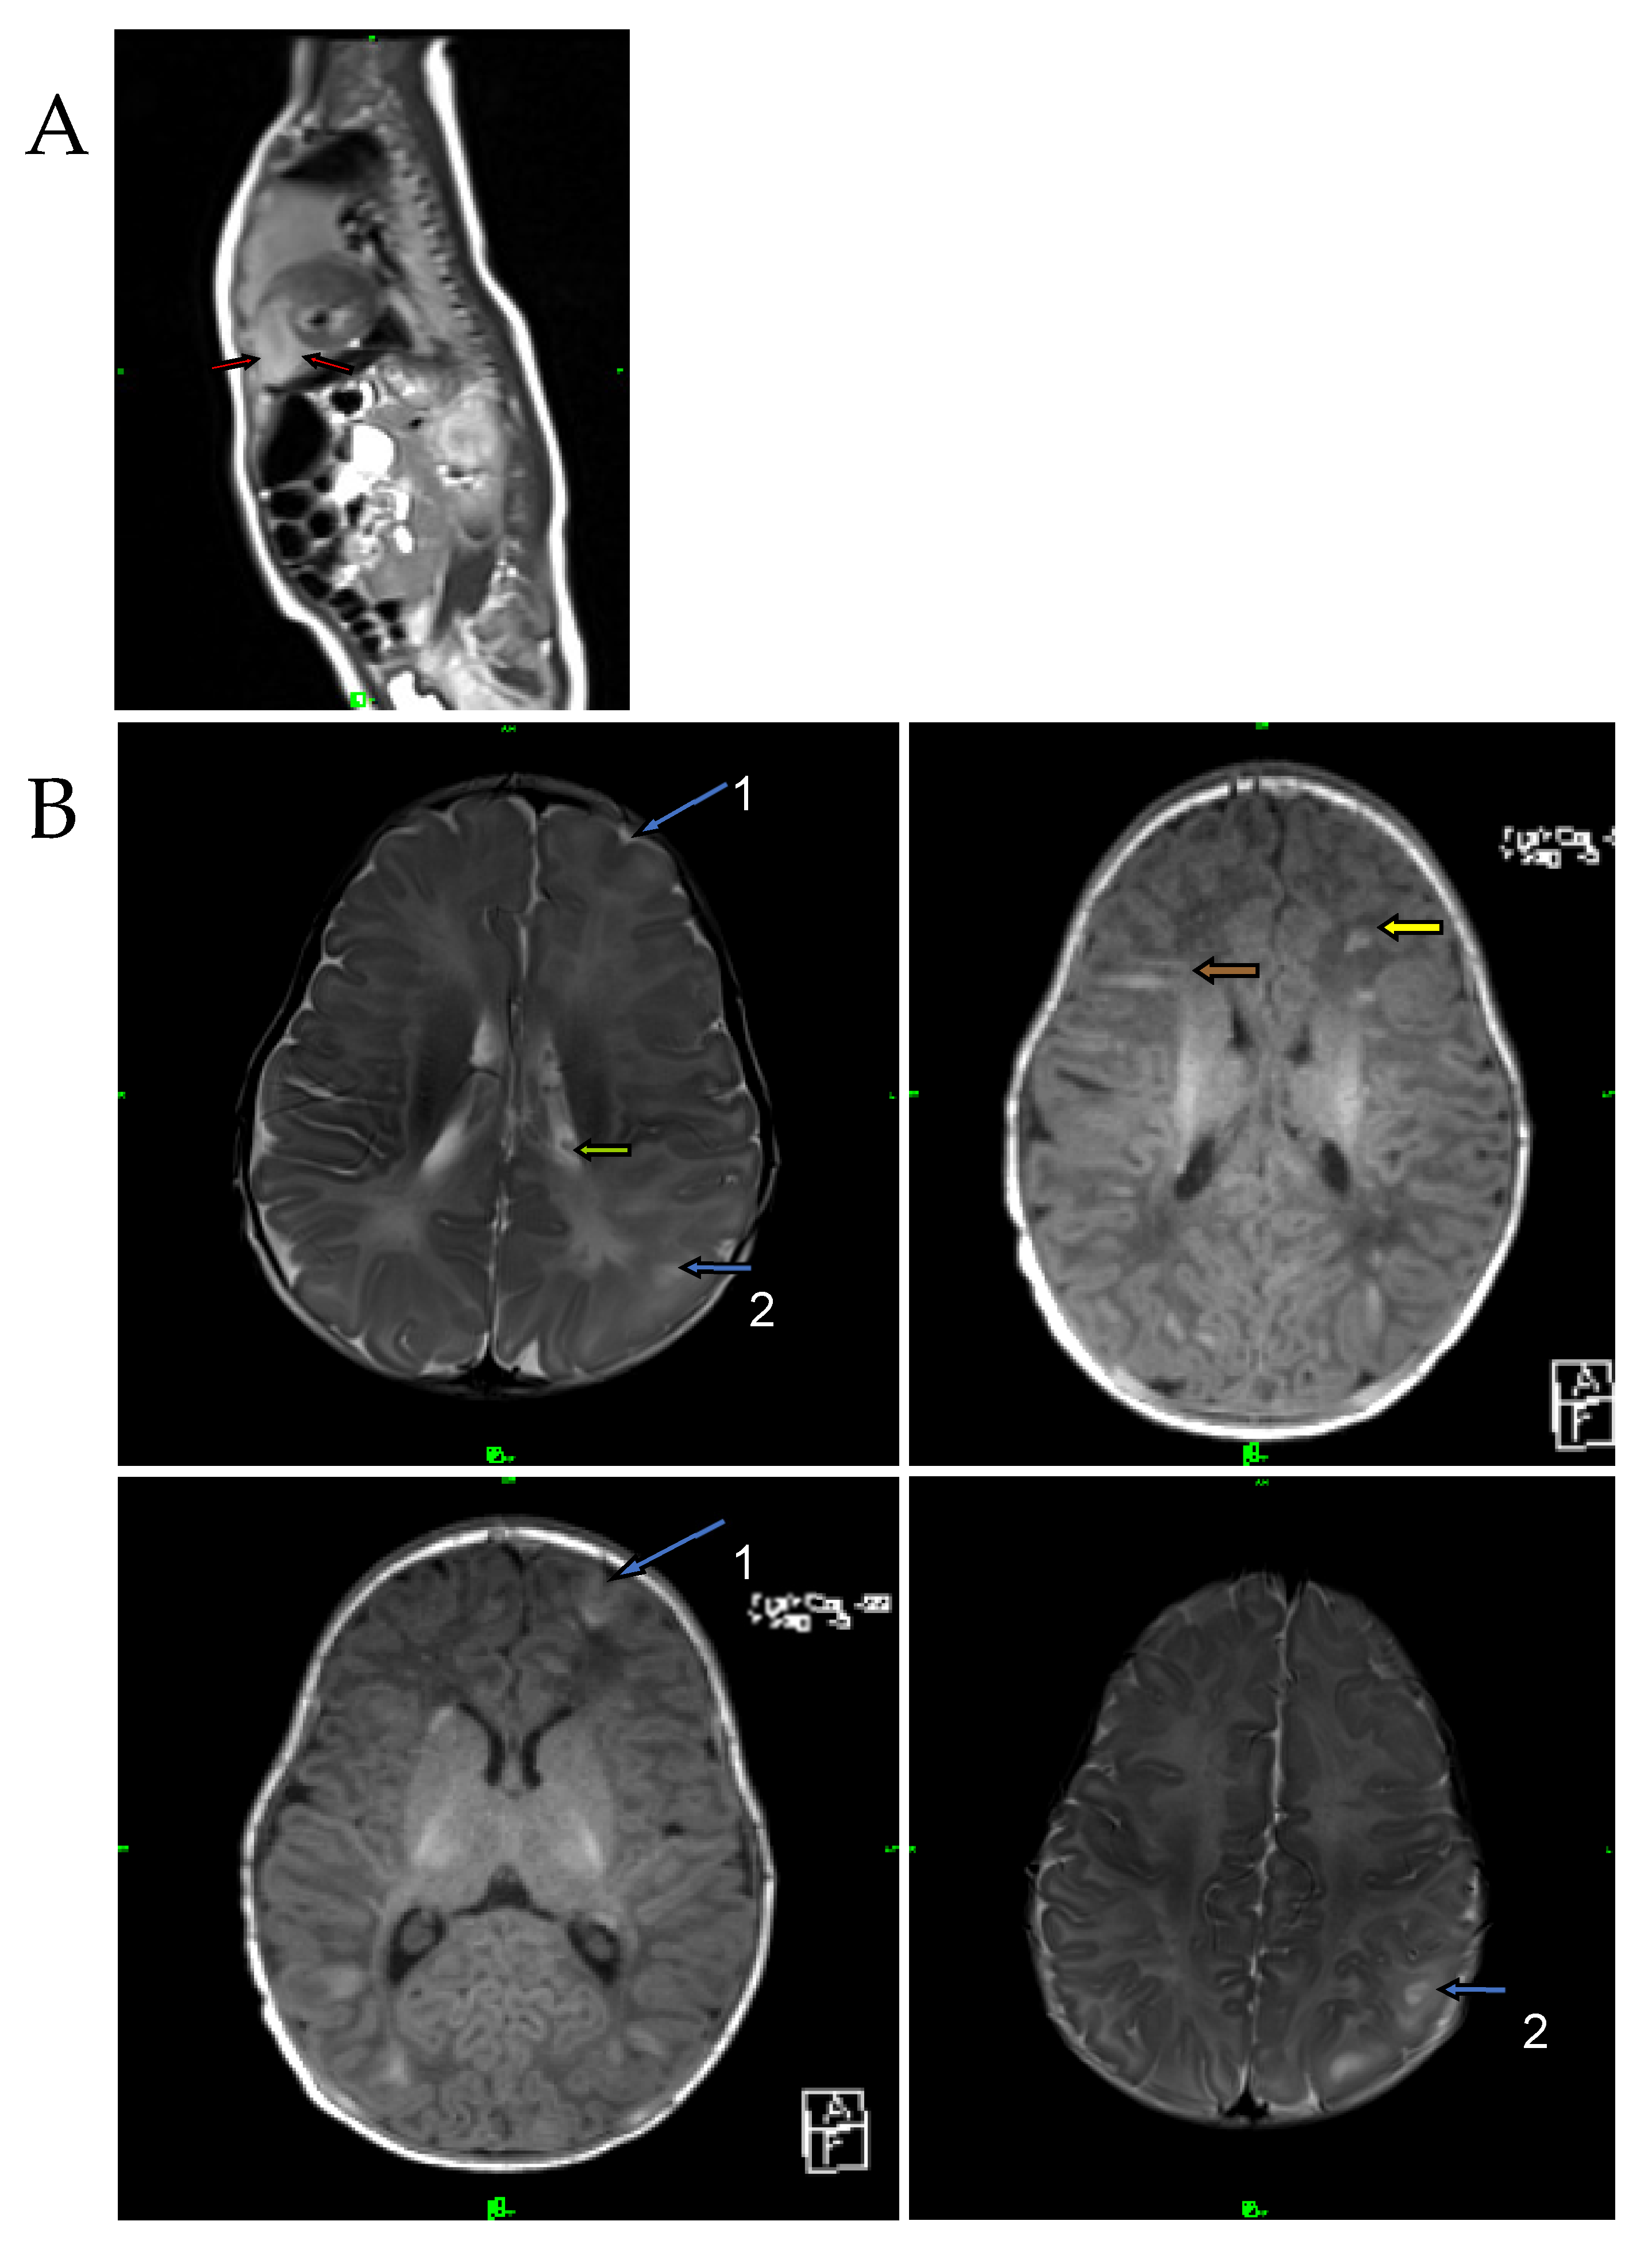

The proband has been under close observation by a neurodevelopmental specialist since birth. The proband has shown good growth and development. An EEG was performed at 4 months and detected peaks that corresponded to the left temporal tuber. West’s syndrome was diagnosed at this age based on the following clinical findings: seizures, clinically detected convulsions, infantile spasms observed by the parents, and hypsarrhythmia on EEG. Attention deficit was not observed in the proband. He became seizure-free following vigabatrin and nitrazepam therapy. The proband was under regular cardiological control, had balanced circulation and did not require any medication. At the one-year MRI follow-up, further regression of the tumor was observed. Mild hypotonia was observed during physical examination. Several hypopigmented patches were observed on the abdominal region. We used the Bayley Scales of Infant and Toddler Development (BSID) to measure his physical, cognitive, socioemotional, linguistic and behavioral skills. The results of the BSID at one year of age showed age-appropriate values (TQ > 100). His speech development was on time. The proband had regular cardiological follow-ups and abdominal ultrasound examinations until he was three years old, with normal results. Cranial MRI examination was performed three times during this period, during which the size of the subependymal nodules and SEGA did not change. When the proband was around the age of three, he underwent examination at the neurology department, due to the growing frequency of seizures. The EEG revealed a slow base activity in the left temporal lobe and revealed left temporal epileptic activity. Carbamazepine supplementation was started for the proband. The BSID at three years of age showed a 6–10 months delay in all the parameters (TQ 89–91).